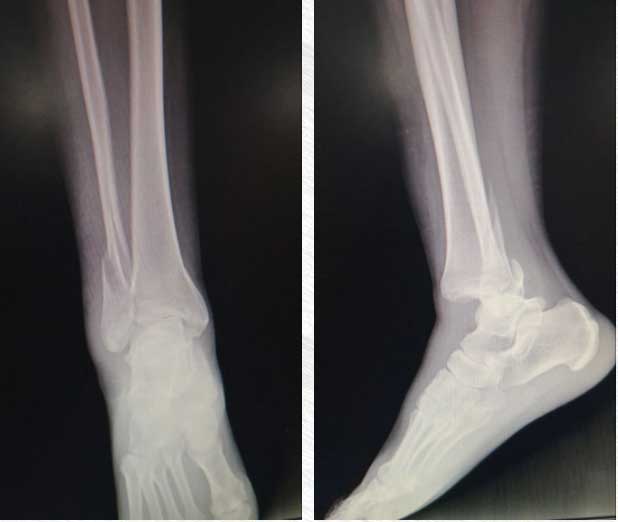

經(jīng)詢(xún)問(wèn),傷者來(lái)自天津,在游玩途中不慎摔倒。傷者右腳受傷,踝關(guān)節嚴重腫脹變形,腳不能沾地受力,經(jīng)驗豐富的陳永明判斷受傷部位骨折,需要進(jìn)一步診療。

當時(shí)天色漸暗,面對焦急、無(wú)措的傷者,陳永明轉身和家人商量,決定提前結束他們的旅行計劃。他對劉女士受傷部位進(jìn)行簡(jiǎn)單處理后,協(xié)助同行人員輪流背扶其慢慢下山、驅車(chē)前往安陽(yáng)市第二人民醫院就醫。通過(guò)檢查,傷者踝關(guān)節嚴重骨折脫位,給予石膏固定、應用止痛藥物等治療。第二天,待病情穩定后,劉女士前往天津當地醫院進(jìn)一步治療。